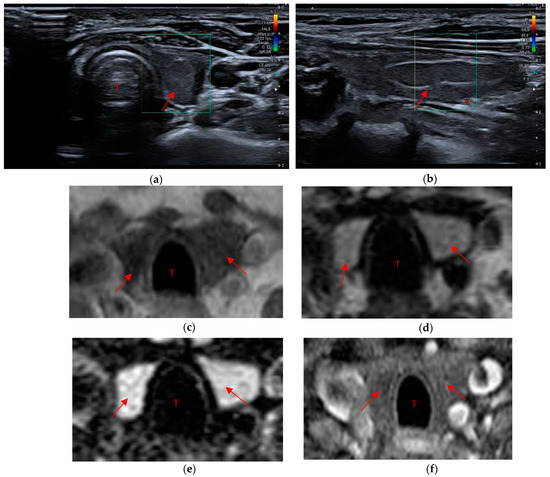

• A markedly hypoechoic pattern with well-defined margins, often with evidence of a peripheral halo (pseudo-capsule appearance), was found in 13 patients, which is approximately 34% of patients with evidence of residual swab (Figure 1a,b).

Figure 1. Residual swab pattern (red arrow) 1, characterized by a markedly hypoechoic pattern with an ecostructure of hyperechoic spots and well-defined margins; (a) Longitudinal view; (b) Axial view. Jugular vein (JV), Carotid artery (CA) and Trachea (T).